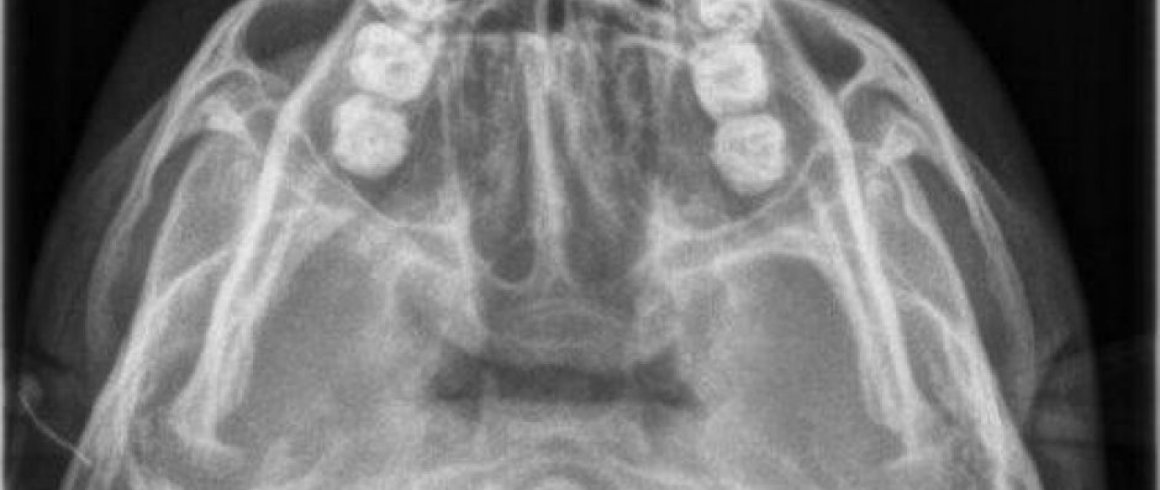

- Senos Maxilares (Waters)

- Análisis Cefalométrico Frontal